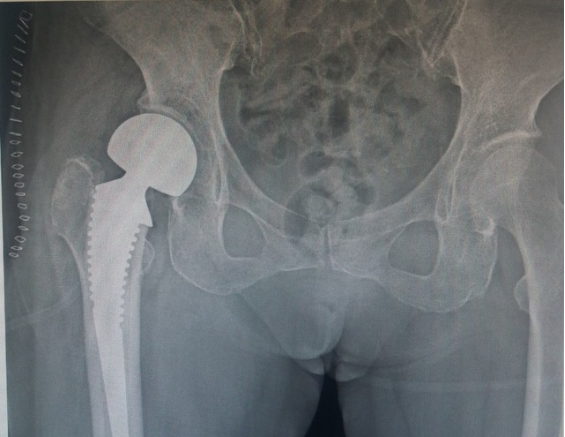

老年人关节内骨折合并骨质疏松症时,软骨下骨质量差,骨折块易嵌入关节面,解剖复位困难,骨折复位在下地负重或关节活动时难以维持,因此内固定治疗效果不佳。此时可酌情选择关节置换治疗,能够获得更好的预后。当骨折未累及关节面,但存在股骨头缺血性坏死风险时,例如股骨头下骨折或肱骨近端骨折,关节置换术的疗效优于内固定[27][28][29]。随着反肩关节置换术的出现,越来越多的骨科医生选择关节置换术治疗复杂的肱骨近端骨折,获得了良好的治疗效果;而肘关节置换术已经成为复杂骨质疏松性肱骨远端骨折的常规治疗手段,临床研究也验证了其优良且可靠的治疗效果[28]。因此,当骨质疏松性骨折骨质量差,骨折碎片较小时,人工关节置换术应首先考虑。